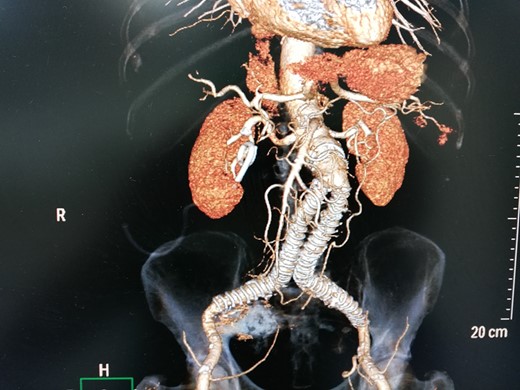

A 78-year-old man was referred in our vascular unit due to an 8.8 cm right IIAA. His medical history included arterial hypertension, diabetes mellitus (non-insulin dependent), right hemicolectomy for adenocarcinoma of ascending colon and EVAR of abdominal aortic aneurysm with Anaconda stent graft (Anaconda, Vascutek, Scotland) 6 years ago followed by deployment of extensions in external iliac arteries with coverage of internal iliac arteries 1 year later in another facility. The patient did not refer any buttock claudication or intestinal disturbances during follow-up. The last control with computed tomography angiography was performed 4 years ago (CTA) depicting a right IIAA, 4.3 cm, which was decided to be managed conservative due to his medical comorbidities. A contrast-enhanced CT was performed in our unit which revealed an 8.8 cm right IIAA with the presence of two runoff vessels deep in the pelvis with direction to the gluteal muscles (Fig. 1). An endovascular embolization of the aneurysm was decided due to his medical history. The patient was fully informed for the endovascular repair, the possible complications of the operation and written consent was obtained.

Contrast-enhanced CT depicted an increase of right IIA to 8,8 cm with type II endoleak from two runoff vessels deep in the pelvic cavity.

3D-CT aortography after 6 months depicted thrombosis of the aneurysm with coil embolization.